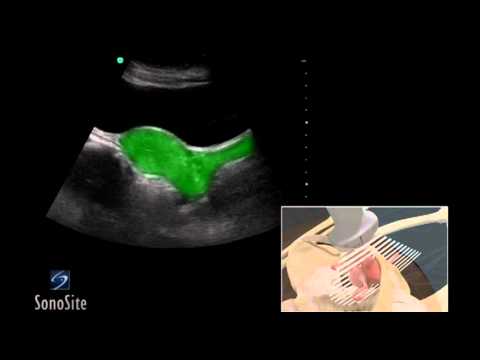

So i finally went to the doctors how many years later. for them to schedule me a pelvic sonogram. For those of you that dont know its topical (1st video) as if they were doing a regular sonogram and then a long stemmed camera is inserted into your vagina where they can look directly at the ovaries. (very invasive/2nd video).